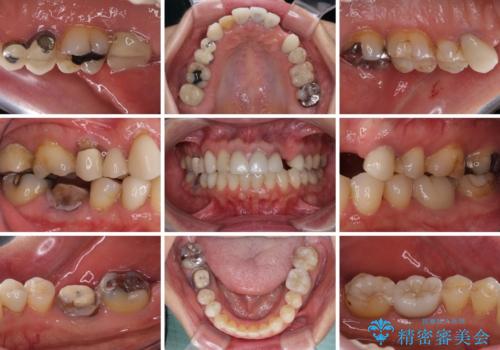

欠損やむし歯の歯をきれいなセラミックに 全顎虫歯治療

- 他院で矯正治療を終えたものの、むし歯や欠損部の治療が進められないとのことで来院された患者様です。

欠損部や、銀歯やむし歯の大きな歯はセラミッククラウンやブリッジに、小さいむし歯はセラミックインレーにて治療を行うこととしました。

歯肉の状態がとても、短期間でスムーズに治療を終えることができました。